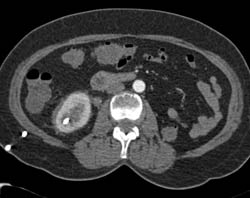

Transplant Kidney With Renal Artery Off Iliac Artery